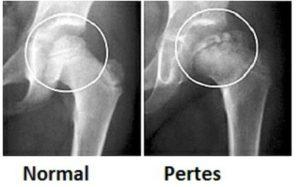

В основе диагностики болезни Легга-Пертеса лежит рентгенологическое исследование сустава, с его помощью специалисты определяют стадию и степень деформации. Согласно полученным результатам врач выбирает оптимальные способы лечения. Дополнительными диагностическими методами служат:

Рентгенологическое обследование

При подозрении на болезнь Пертеса делают не только снимки в стандартных проекциях, но и рентгенограмму в проекции Лауэнштейна. На основании полученных результатов исследования врач ставит диагноз, чаще всего используя классификации Сальтера-Томсона и Кэттерола.

Ортопед, изучая рентгенограмму, выявляет особенности строения костей и степень деформации суставной головки.

Снимки позволяют увидеть метафизарные изменения, линию субхондрального перелома и другие патологии.